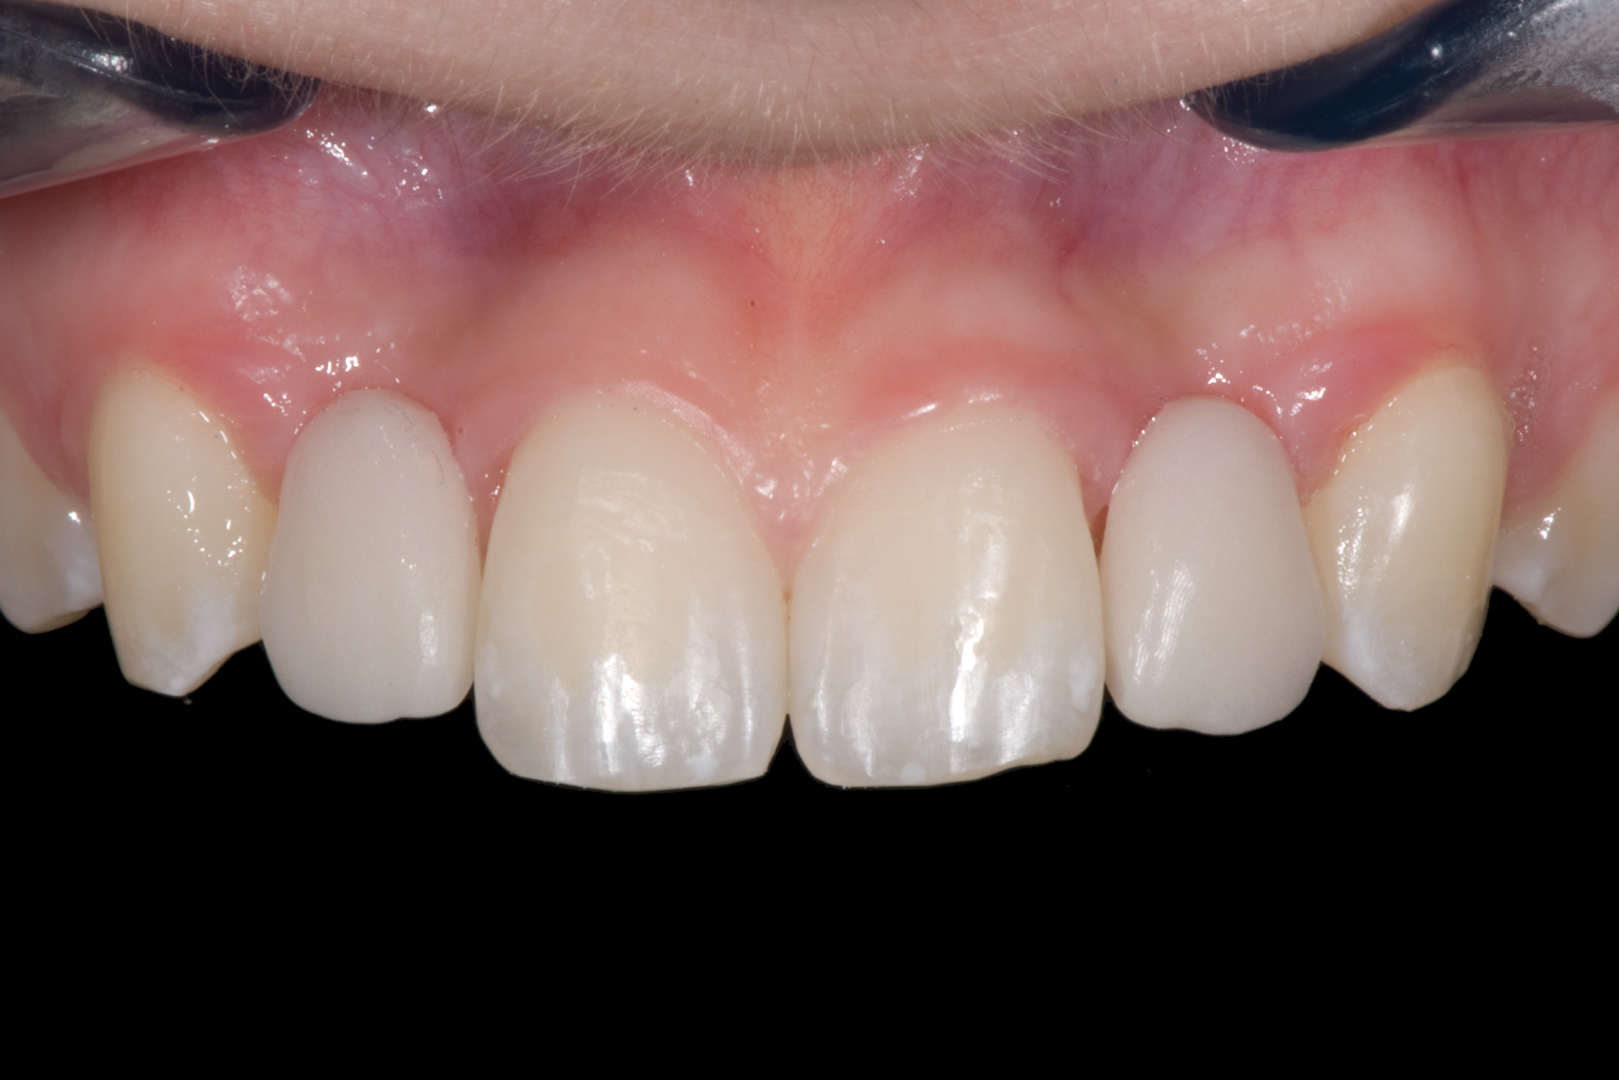

Fig 12. 15-year-old girl after orthodontic therapy idealized maxillary lateral incisor spaces.

Figure 12